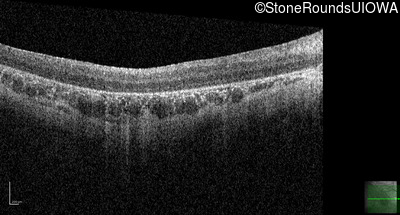

Optical Coherence Tomography - Right - 10/300 sc

Exemplar / OCT Stack

OCT Stack